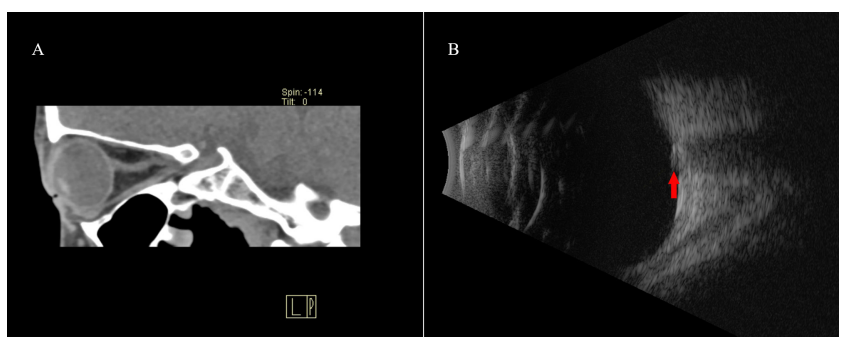

图 7 一例 PHOMS 的 CT 和超声影像

Figure 7 CT and ultrasound images of PHOMS.

PHOMS 患者眼眶 CT 未见异常 ( 图 A);眼球超声可见眼球后壁视乳头 ( 视盘 ) 前隆起结构 ( 红色箭头 ),其中无高信号回声 ( 图 B)。

Orbital CT of PHOMS of a patient was unremarkable (figure A). The ultrasound showed a tuberosity of optic disc (figure B, red arrow) on the posterior wall of the eyeball, and there was no hyperechoic structure.